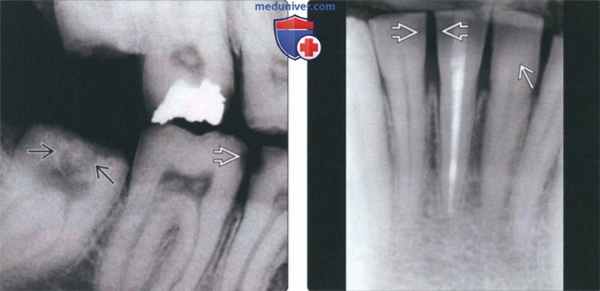

(Слева) На рентгенограмме с использованием межзубного фикса тора эмаль практически не определяется. Обратите внимание на кариозные поражения и очевидную резорбцию окклюзионных поверхностей частично прорезавшегося третьего моляра. Резорбция непрорезавшихся зубов наблюдается при гипопла-стическом типе несовершенного амелогенеза.

(Справа) На периапикальной рентгенограмме резцов нижней челюсти визуализируется очень тонкий слой эмали - типичный признак гипопластического типа несовершенного амелогенеза. Обратите внимание на открытые контакты и левый боковой резец в виде прямоугольника.